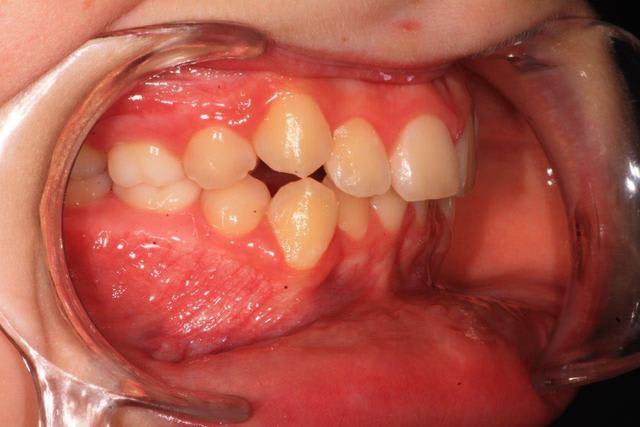

Au niveau ODF , il y a une cl 2 bout a bout avec supra, malposition canine.

Il faudrait plus d'éléments pour répondre ( télé profil, pano, photos endo et exo buccales)

Si il s'agit d'une classe II.2 :

- le condyle se retrouve très souvent en rétro position forcée à cause de l'inclinaison des incisives maxillaires

- dans une luxation discale : le disque se retrouve "en avant" du condyle

- le patient étant en classe II, en cours de croissance, il y a tout intérêt à essayer de le faire propulser, au lieu de "distaler" les molaires maxillaires ( encore un mythe...)

Toutes les études sérieuses sur les relations ODF-ATM montrent l'absence de liens clairs entre les deux, maintenant un minimum de bon sens clinique devrait nous encourager à retrouver un guidage antérieur non traumatogene

Donc :

- lever les verrous de croissance ( sens T : expansion si besoin, sens V: levée de la supra, sens AP : donner un torque correct aux incisives sup )

- si besoin : mettre en place un système de propulsion

quelques documents :